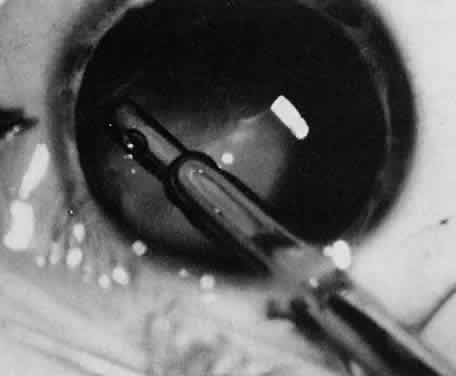

Usually, anterior polar cataracts are visually insignificant and allow normal visual development (see Fig. 1). However, some affect vision, and all require careful monitoring.7 Centrally located cataracts that are on or near the posterior lens capsule have a greater effect on the refraction of light and visual acuity (Fig. 2). Nuclear cataracts associated with metabolic disorders or prenatal infections produce double refracting systems that cause optical distortion and significantly decrease visual acuity (Fig. 3).